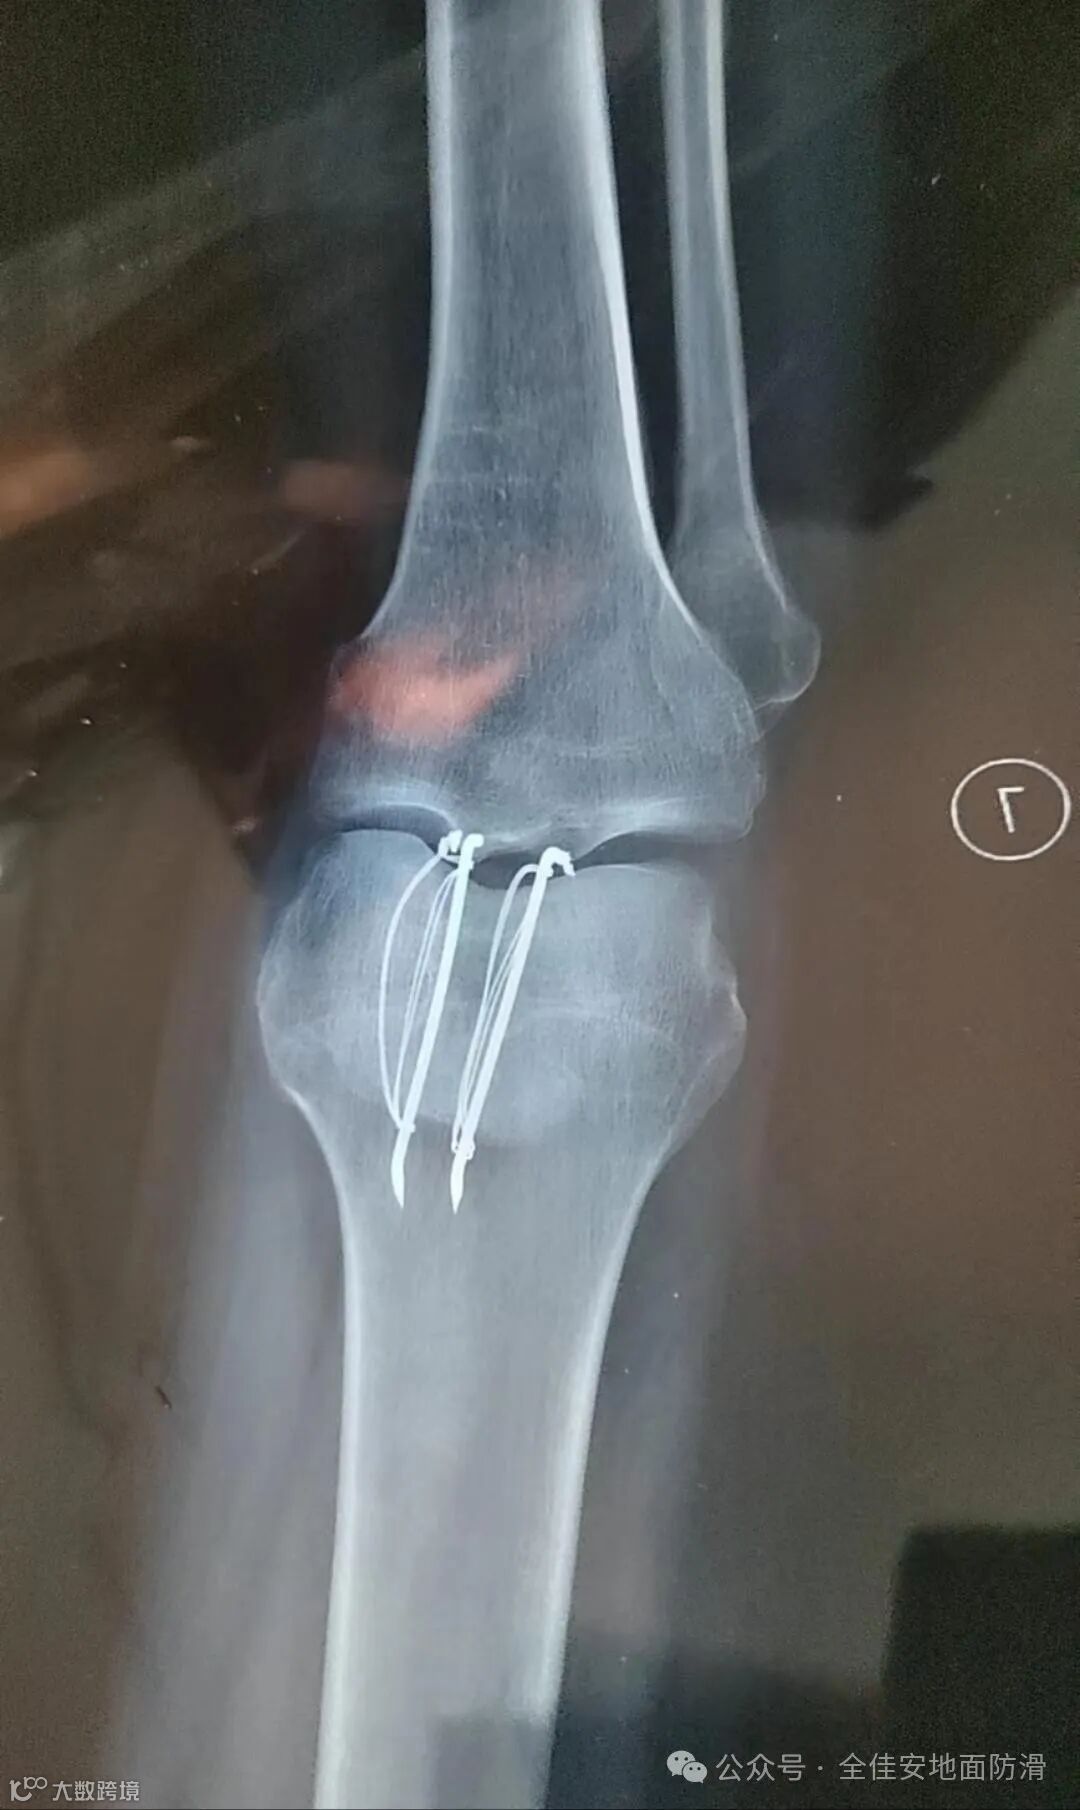

5月17日下午,周先生向记者展示了他左腿膝盖的伤疤,“缝了11针,在医院呆了7天,在家躺了两个月,左腿肌肉萎缩,我现在还不能下蹲和正常上下楼梯。”